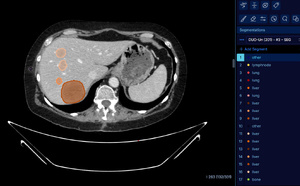

En reliant l’IA aux pratiques cliniques, Dedalus fait la différence en imagerie médicale

Acteur majeur européen de la santé numérique, Dedalus a fait de l’imagerie médicale un axe stratégique prioritaire. En France, le groupe a structuré une Business unit (BU) dédiée et lancé une nouvelle génération de solutions intégrant pleinement les technologies d’intelligence artificielle. Parmi...

Dedalus et les Hospices Civils de Lyon s’associent pour transformer l’imagerie médicale avec la solution DeepUnity

Le groupe Dedalus, acteur européen majeur de solutions logicielles en santé, et les Hospices Civils de Lyon (HCL) scellent un partenariat stratégique de plus de dix ans pour le déploiement du PACS (Picture Archiving and Communcation System) étendu DeepUnity. Objectif : faire de l’imagerie médicale...